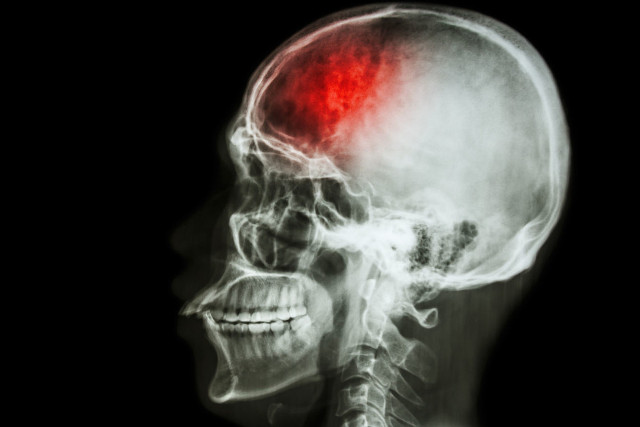

Các nhà nghiên cứu tại Đại học Georgia đã phát triển phương pháp điều trị dựa trên tế bào gốc mới cho bệnh đột qụy. Khi được thử nghiệm trên mô hình động vật, kỹ thuật này cho thấy có thể làm giảm tổn thương não và giúp não tự lành nhanh hơn, và kết quả đã hứa hẹn đủ để thử nghiệm lâm sàng trên người ngay trong năm sau.

Theo CDC, đột qụy ảnh hưởng đến gần 800.000 người mỗi năm ở Mỹ, và khoảng 140.000 chết, do đó làm cho nó là nguyên nhân thứ năm gây tử vong ở nước này.